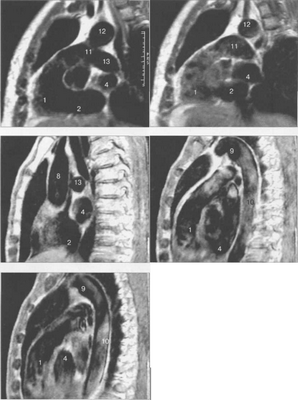

Рис. 9.47. МРТ сердца. Аксиальная плоскость.

Здесь и на рис. 9.48—9.52:

I — правый желудочек, 2 — левый желудочек, 3 — правое предсердие, 4 — левое предсердие, 5 — межжелудочковая перегородка, 6 — межпредсердная перегородка, 7 — задняя стенка левого желудочка, 8 — восходящая часть аорты, 9 — дуга аорты, 10 — нисходящая часть аорты, 11 — легочный ствол, 12 — правая легочная артерия. 13 — левая легочная артерия, 14 — верхняя полая вена, 15 — нижняя полая вена, 16 — трахея.

Рис. 9.48. MPT сердца. Сагиттальная плоскость.

Рис. 9.49. МРТ сердца. Двухкамерные сечения.

Рис. 9.50. МРТ сердца. Фронтальные сечения.

Рис. 9.51. МРТ сердца. Сечения по короткой оси левого желудочка.

Рис. 9.52. МРТ сердца. Четырехкамерные сечения.

На рис. 9.47—9.52 представлены Т1-ВИ наиболее часто используемых МР-сечений сердца.